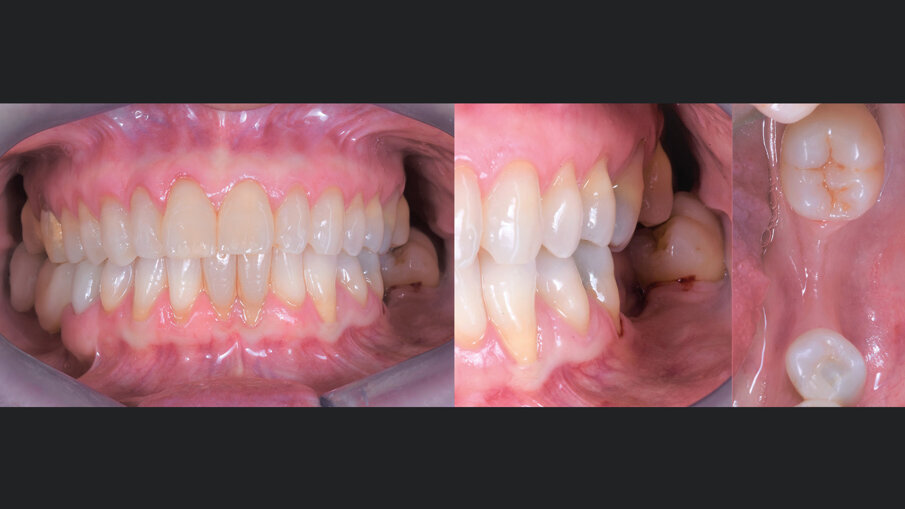

Gli innesti eterologhi utilizzati, ottenuti mediante un processo di deantigenazione enzimatica (Zymo-Teck, Bioteck) sono caratterizzati dalla presenza della componente minerale inalterata e del collagene osseo in conformazione nativa. Grazie a queste proprietà, l’innesto viene riconosciuto fisiologicamente da osteoclasti ed osteoblasti3 e viene rimodellato con osso del paziente in tempi fisiologici4, 5. Inoltre, la lamina corticale di origine equina, subisce un ulteriore trattamento di parziale demineralizzazione, che espone il collagene preservato e ne permette la caratteristica flessibilità che la rende facilmente adattabile alle diverse geometrie della cresta alveolare6, 7. Veniva quindi inserito un impianto (Straumann Tissue Level 4,5 x 8,5 mm), l’ISQ di 79 suggeriva la simultanea inserzione della vite di guarigione e tre mesi più tardi veniva consegnata la protesi definitiva in zirconia (Figg. 6-8). A 24 mesi dalla consegna della protesi, veniva eseguita una RX di controllo che mostrava un ottimo mantenimento volumetrico dell’osso alveolare (Fig. 9).

Fig. 8 - Inserimento di una corona in zirconio monolitico avvitata su impianto. Si osserva un ottimo mantenimento volumetrico dei tessuti molli.